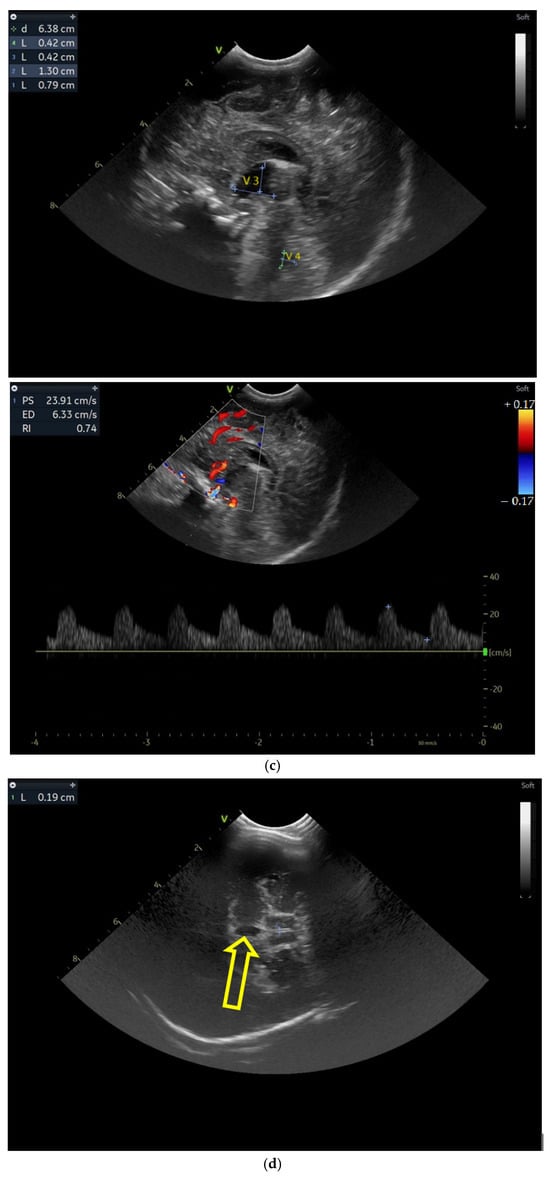

Case 4 involved a 37-week gestational age infant born from a mother with Toxoplasma gondii infection during pregnancy who was delivered through C-section due to failed spontaneous birth. The IgM antibodies were negative at birth and the newborn was treated for Toxoplasma one month after birth.

Five weeks after birth, the patient presented for the first cranial ultrasound examination, which revealed enlarged ventricles and the presence of a hyperechoic image in the right frontal lobe, suggestive of calcifications. The parenchymal tissue was reduced (Figure 4a–d). The anterior fontanelle was wide, with large sutures. The neurological assessment showed that the infant could keep eye contact and would also hold its head during the traction-to-sit maneuver but was not able to lift its head while in the prone position. The passive tone assessment showed the “scarf sign”, with the elbow at the midline and a popliteal angle range for both legs of 90–100°. Deep tendon reflexes were present. The general movement (GM) assessment revealed a poor repertoire pattern with minimal mobility in the lower limbs. Treatment for Toxoplasma was initiated.

Figure 4.

(a) Cranial ultrasound. Coronal view. Lateral ventricles and third ventricle enlargement. L1, L2—Levine index measurement. L3, L4—posterior horn of the lateral ventricles’ width measurement. L5—third ventricle width measurement (personal image collection). (b) Cranial ultrasound. Sagittal view. Enlarged third and fourth ventricles. L1, L2—third ventricle measurements. L3, L4—fourth ventricle measurements (personal image collection). (c) Cranial ultrasound. Sagittal view. Enlarged lateral ventricles. Up—left ventricle. Down—right ventricle (personal image collection). (d) Cranial ultrasound. Coronal view. Punctuate hyperechoic images were observed in the right lobe (personal image collection). (e). Up left—MRI T1 sequence. Up right—MRI T2 sequence—susceptibility weight imaging (SWI). Down—CT scan. Transversal view. Yellow arrows—multiple calcifications can be seen in the CT scan (personal image collection). (f) Cranial ultrasound. Coronal view. Lateral ventricles. L1, L2—Levine index measurement. L3, L4—anterior horn width measurement. Blue arrow—intraventricular shunt (personal image collection). (g) Cranial ultrasound. Sagittal view. Thalamo-occipital distance measurements. Up—right ventricle. Down—left ventricle (personal image collection).

At six weeks after birth, an MRI scan was performed, while a CT scan was performed at 14 weeks of life, both providing valuable information regarding the sequelae of Toxoplasmosis (Figure 4e). Even though a few signs were observed on the MRI, the CT scan better outlined the presence of the parenchymal calcifications. A neurosurgical intervention was intended, a ventricle puncture was performed, and a shunt was placed in the right ventricle. The cranial ultrasound at two months of life did not show notable improvements, however (Figure 4f,g). The neurological examinations showed axial hypotonia and limb hypertonia.